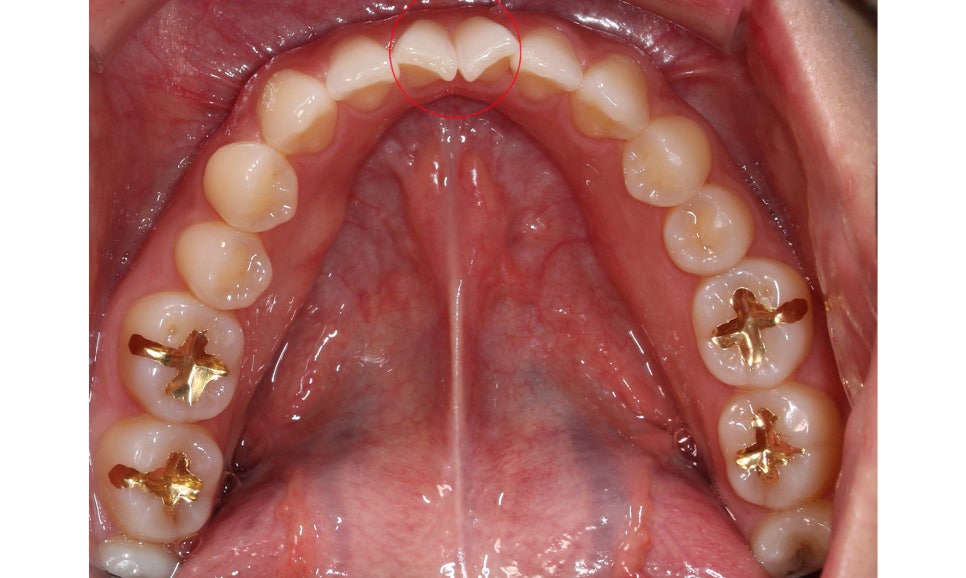

하악 교합면은 위처럼 앞쪽의 중절치가

마주 보듯이 회전되어 있는 모습으로

최후방의 어금니(사랑니)를 발치하여

공간을 확보할 예정입니다.